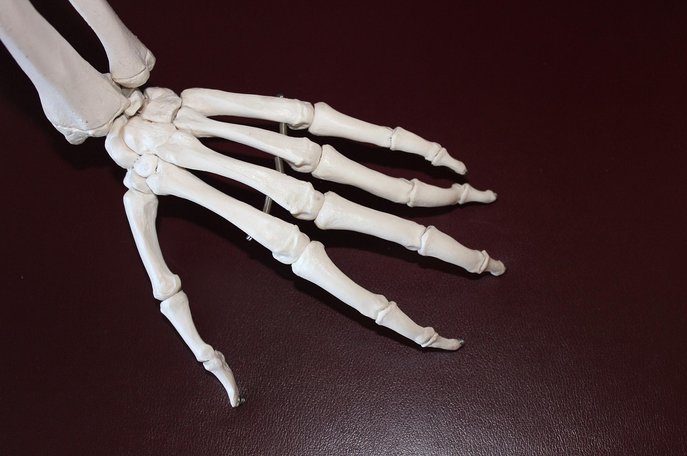

관절은 뼈와 뼈가 만나는 부분으로, 우리 몸이 자유롭게 움직일 수 있도록 돕는 핵심적인 구조물입니다.

무릎, 어깨, 고관절, 손목 등 우리 몸에는 200개가 넘는 관절이 존재하며, 이들은 일상생활의 모든 동작에 관여합니다.